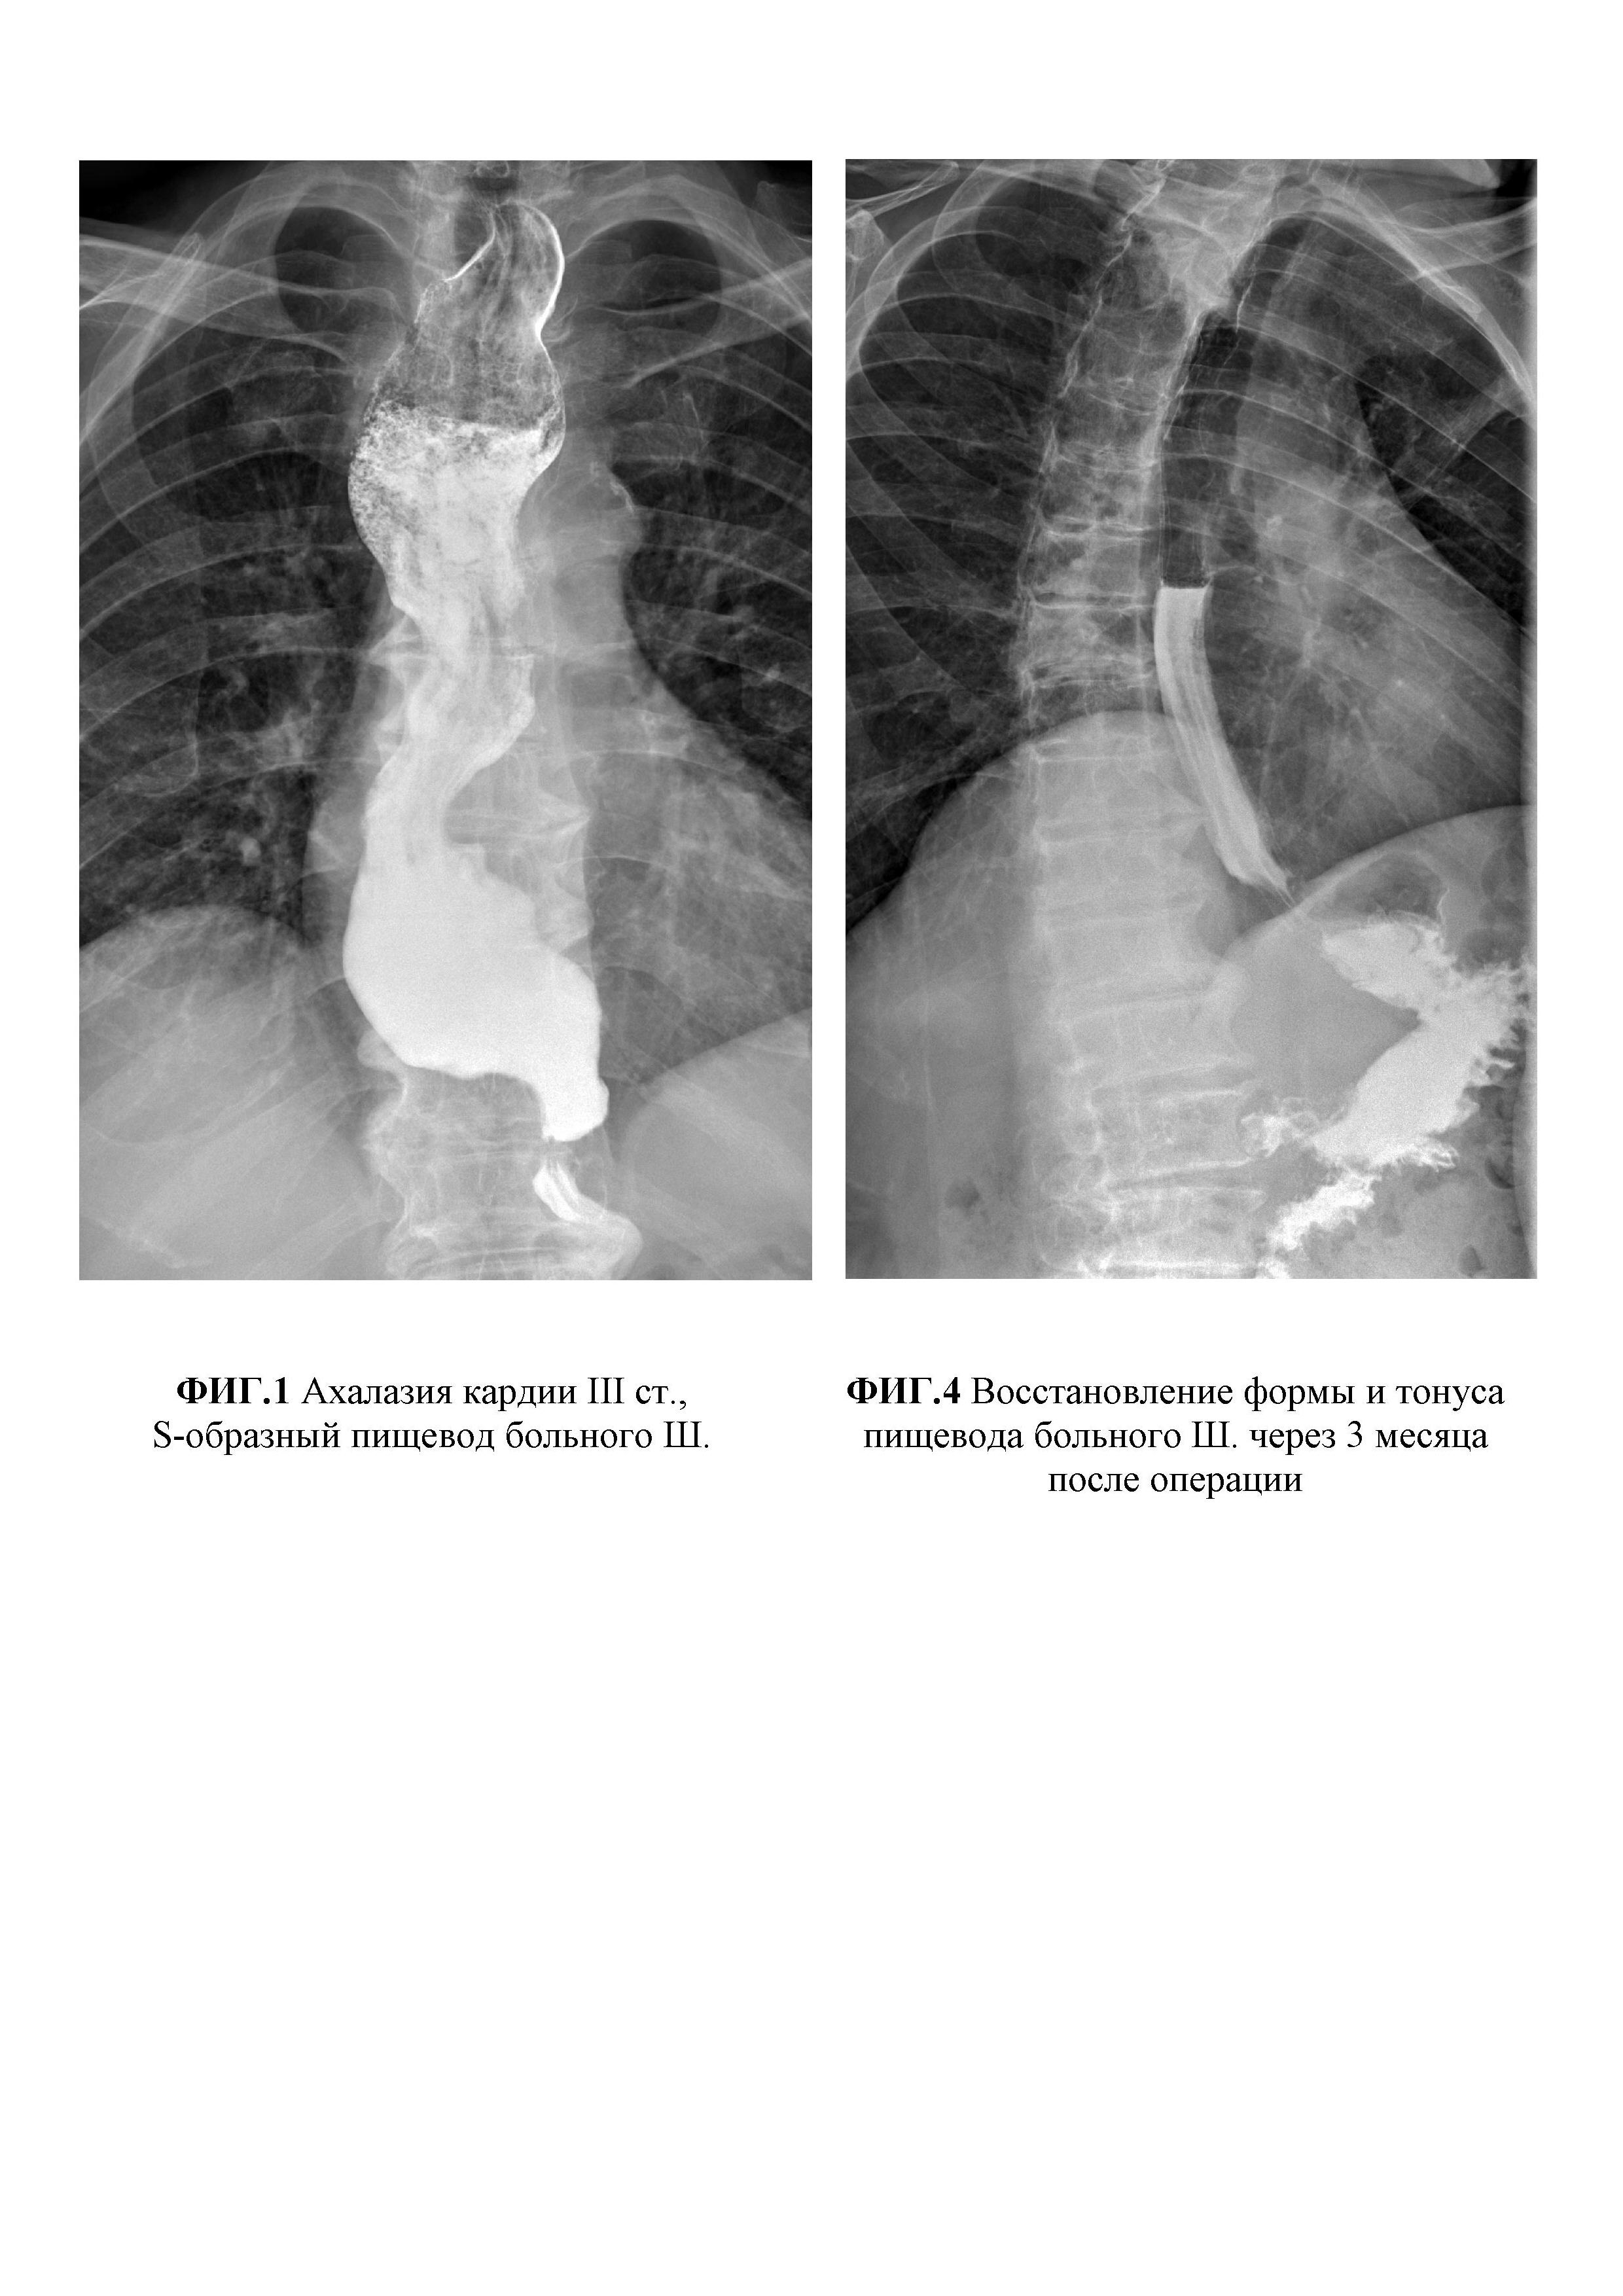

Изобретение относится к области медицины, а именно к хирургии и может быть использовано в оперативном лечении ахалазии кардии III-IV стадии с S-, L-образной деформацией пищевода. Известно много способов хирургического лечения тяжелых форм ахалазии кардии с декомпенсацией моторно-эвакуаторной функции и изменением анатомии пищевода, начиная от малоинвазивных вмешательств, например, операции Геллера, до сверх радикальных - демукозации или экстирпации пищевода. Опыт показывает, что операция Геллера низкоэффективна из-за частых рецидивов заболевания. Экстирпация и демукозация пищевода, не смотря на свою радикальность, сопряжены с опасными гнойными осложнениями, которые зачастую могут стать причиной смерти больного в раннем послеоперационном периоде. Наиболее близким по техническому решению к заявляемому способу является способ хирургического лечения ахалазии кардии III-IV стадии (патент №224217 от 25.02.2003 «Способ хирургического лечения ахалазии кардии III-IV стадии»; авторы: Кошель А.П., Жерлов Г.К., Зыков Д.В., Райш Д.В., Рыжов А.И., Артеменко М.В.), включающий мобилизацию и демускуляризацию суженной кардии и на 1,5 см проксимальнее и дистальнее места сужения на пищеводе и желудке, а также инвагинацию узловыми швами демускуляризированного подслизисто-слизистого участка в виде клапана. Данный способ имеет ряд существенных недостатков. При выполнении операции не производится низведение нижнегрудного отдела пищевода, что не оказывает влияние на расширение и девиацию пищевода. Демускуляризация суженной кардии, а также прилегающих к ней полутора сантиметров на пищеводе и желудке является недостаточным для тяжелых форм ахалазии кардии, ассоциированных с выраженной мышечной гипертрофией и декомпенсацией моторно-эвакуаторной функцией. При создании клапана не происходит образование угла Гиса и не восстанавливается естественный ход мышечных волокон кардиального сфинктера. Кроме того, формируемый клапан суживает просвет за счет сшивания над ним гипертрофированного мышечного слоя пищевода с серозно-мышечной оболочкой желудка в 1,5 см от кардии, где просвет желудка недостаточно широк. Таким образом, данный способ не может быть применим для хирургического лечения тяжелых форм ахалазии кардии с декомпенсацией моторно-эвакуаторной функции ввиду высокой вероятности рецидива заболевания. Задачей, решаемой предложенным изобретением, является разработка радикального способа лечения ахалазии кардии III-IV стадии, осложненной S-, L-образной деформацией пищевода за счет устранения расширения и искривления пищевода, восстановления его формы и тонуса, а также замыкательной и арефлюксной функции пищеводно-желудочного перехода. Новый технический результат достигают способом хирургического лечения ахалазии кардии III-IV стадии, осложненной S-, L-образной деформацией пищевода заключающийся в мобилизации и демускуляризации пищеводно-желудочного перехода вокруг зоны сужения, формирования инвагинационного клапана путем погружения демускуляризированного слизисто-подслизитого слоя узловыми швами, отличающийся тем, что путем тракции за турникет производят пристеночную мобилизацию и низведение нижнегрудного отдела пищевода до состояния его умеренного натяжения; циркулярно рассекают серозно-мышечную оболочку передней и задней стенок желудка в 3,5 см от кардии; от края разреза производят удаление серозно-мышечной оболочки желудка и низведенного пищевода в виде "чулка" на протяжении 16 см; демускуляризированный участок слизисто-подслизистого слоя инвагинируют в просвет желудка с помощью 6-ти узловых швов, наложенных по линии соприкосновения мышечных оболочек пищевода и желудка; на передней стенке желудка на 14 мм ниже швов выкраивают несвободный серозно-мышечный лоскут длиной 45 мм, шириной 20 мм с осевым типом кровообращения в области дна желудка; подслизистую площадку после выкраивания лоскута ушивают; серозно-мышечный лоскут проводят между левой стенкой пищевода и дном желудка на заднюю стенку с фиксацией лоскута на передней стенке желудка ниже его основания в фазе умеренного натяжения. Новым в изобретении является то, что путем тракции за турникет производят пристеночную мобилизацию и низведение нижнегрудного отдела пищевода до состояния его умеренного натяжения; циркулярно рассекают серозно-мышечную оболочку передней и задней стенок желудка в 3,5 см от кардии; от края разреза производят удаление серозно-мышечной оболочки желудка и низведенного пищевода в виде "чулка" на протяжении 16 см; демускуляризированный участок слизисто-подслизистого слоя инвагинируют в просвет желудка с помощью 6-ти узловых швов, наложенных по линии соприкосновения мышечных оболочек пищевода и желудка; на передней стенке желудка на 14 мм ниже швов выкраивают несвободный серозно-мышечный лоскут длиной 45 мм, шириной 20 мм с осевым типом кровообращения в области дна желудка; подслизистую площадку после выкраивания лоскута ушивают; серозно-мышечный лоскут проводят между левой стенкой пищевода и дном желудка на заднюю стенку с фиксацией лоскута на передней стенке желудка ниже его основания в фазе умеренного натяжения. Разработанный способ позволяет восстановить анатомическую форму и тонус пищевода за счет ликвидации мешкообразного расширения и петлеобразования внутригрудной части пищевода. Вследствие демускуляризации и сокращения серозно-мышечного слоя по краю резекции создается протяженный участок оголенной подслизистой основы: 10 см на пищеводе и 6 см - на желудке. Механизмы восстановления тонуса атоничного пищевода связаны с натяжением и выпрямлением внутригрудной части пищевода в процессе его низведения и инвагинации демускуляризированного подслизисто-слизистого слоя на всем его протяжении (не менее 16 см) в просвет желудка. Положительный эффект и профилактика рецидива заболевания достигается обширной демускуляризацией низведенного сегмента пищевода и верхней трети желудка, а также широким соустьем мышечных оболочек пищевода и верхней трети тела желудка. Фактически гипертрофированная мышечная оболочка пищевода растягивается с помощью 6 узловых швов при адаптации ее по краю серозно-мышечной оболочки верхней трети желудка, диаметр которой на данном участке не менее 7 см. Создание клапана из слизисто-подслизистого слоя, который вследствие ретракции тканей сокращается до 3,5 см, в сочетании с компрессией серозно-мышечным лоскутом в области левой, задней и правой стенок пищеводно-желудочного перехода обеспечивает восстановление замыкательной и арефлюксной функции. Клинический пример Больной Ш., 62 лет находился на лечении в клинике общей хирургии ФГБОУВО СибГМУ с диагнозом основного заболевания: ахалазия кардии III ст., стадия субкомпенсации, S-образный пищевод. Сопутствующая патология: ишемическая болезнь сердца, стенокардия напряжения (ФК2), постинфарктный кардиосклероз (2004 г.); хроническая сердечная недостаточность IIA; гипертоническая болезнь III ст., риск 4; хроническая обструктивная болезнь легких, стадия ремиссии. Госпитализирован в плановом порядке для оперативного лечения с жалобами на дисфагию в виде затруднения прохождения пищевого комка, сопровождающееся дискомфортом, иногда болью за грудиной, отрыжкой, неприятным запахом изо рта, снижением массы тела. Из анамнеза известно, что считает себя больным более 5 лет, когда стал отмечать затруднение прохождения пищи после глотания. Для облегчения проглатывания пищевого комка запивал небольшим количеством воды. Иногда вызывал рвоту при задержки пищевого комка, сопровождающегося чувством переполнения или распирающей болью за грудиной. Заболевание развивалось медленно, пациент состоял под наблюдением у гастроэнтеролога поликлиники по месту жительства, периодически проходил обследование и амбулаторное лечение. За последние 2,5 года похудел на 40 кг (до заболевания масса тела 105 кг; в настоящее время весит 65 кг). В связи с прогрессированием заболевания пациент направлен в клинику общей хирургии для оперативного лечения. Данные инструментальных исследований. Рентгеноскопия пищевода и желудка от 22.01.2018 г. При осмотре грудной клетки обращает внимание расширение срединной тени вправо, виден воздух и уровень жидкости в пищеводе, что подтверждается при приеме первого глотка контрастной взвеси. Акт глотания не нарушен. Пищевод имеет S-образную форму, значительно расширен на всем протяжении - натощак 30-35 мм, при исследовании с контрастом - 50-60 мм, заполнен остатками пищи и слизью, заканчивается конусовидным сужением. Кардия сужена примерно до 7-9 мм, первый глоток пропускает через 6 минут от начала исследования, затем длительный спазм и следующий глоток проходит через 9-10 мин. При отсроченном исследовании через 2 часа и 4 часа в пищеводе сохраняется 2/3-1/2 контраста. Сократительная функция пищевода резко нарушена. Складки рельефа не удается увидеть даже через 3,5 часа. В начале исследования газовый пузырь желудка вообще не виден. Сохраняется стойкое сужение на уровне кардии, максимально определяемая ширина 13 мм, здесь видны продольные складки, контуры пищевода ровные, плавные, но на уровне субкардии и малой кривизны неотчетливо контрастированы фрагменты стенки с подрытыми, неровными контурами. В желудке видны фрагменты контрастной взвеси в виде хлопьев в содержимом желудка, контуры стенок, рельеф не определяются. Желудок маленьких размеров, через 4 часа видны следы контраста в двенадцатиперстную кишку. Судить о размерах и состоянии желудка, двенадцатиперстной кишки не представляется возможным. Через 24 часа в пищеводе контрастной взвеси нет, но при этом сохраняется его выраженное расширение и наличие воздуха и жидкости натощак. Вся контрастная взвесь распределена по толстой кишке до сигмовидной. Заключение: Ахалазия кардии III ст., стадия субкомпенсации. Эзофагит, супрастенотическое расширение пищевода с S-образной деформацией (фиг. 1). Эзофагогастродуоденоскопия с эндосонографией пищевода (OLYMPUS EVISEXERA - III, Olympus EU-ME 1, OLYMPUSGIFH-180, Olympus UM-DP20-25R) от 25.04.2018 г. Осмотр с использованием узкого спектра (NBI). Вход в пищевод свободен. В просвете остатки пищи. Пищевод верхней трети расширен до 4-4,5 см, проходим до нижней трети, где просвет щелевидный за счет стойкого спазма. С небольшим форсированием удается пройти к кардии. Слизистая белесовато-розовая с участками гиперкератоза. Зона переходного эпителия четкая, ровная, расположена в 40 см от резцов. На момент осмотра хиатальное отверстие диафрагмы смыкается полностью, соответствует зоне переходного эпителия. Желудок расправился воздухом, стенки эластичные, в просвете небольшое количество прозрачной жидкости. Перистальтика прослеживается равномерно во всех отделах, в антральном отделе круговыми волнами. Слизистая желудка розовая, блестящая, ямочный рисунок четкий, желудочные поля не расширены, складки правильные, расправляются свободно. При ретрофлексии слизистая кардии полностью обхватывает тубус гастроскопа. Угол не деформирован. В препилорической части антрального отдела на малой кривизне эрозия на возвышенном основании 9×10 мм, с углубленным участком в центре, с гематином (биопсия 1 фр.+1 ст.). Подобная эрозия на большой кривизне. Привратник сомкнут, проходим свободно. Луковица двенадцатиперстной кишки достаточного объема, на верхней стенке бруннерома 6×7 мм, на нижней стенке бруннерома 6×7мм с фибрином в центре. Слизистая луковицы двенадцатиперстной кишки гиперемирована, с острыми эрозиями 2-3 мм, покрытыми фибрином (биопсия 2 фр.+2 ст.). Слизистая подковы розовая, бархатистая, рельеф соответствует тонкокишечному. На момент осмотра в просвете двенадцатиперстной кишки желчь. Перистальтика ослаблена. Большой дуоденальный сосок в типичном месте, не изменен. В заключение проведена эндосонография пищевода. Тубус эндоскопа введен в пищевод, просвет заполнен водой, проведено сканирование стенок датчиком с частотой 20 МГц. В верхней трети стенка равномерно пятислойная с толщиной 3,2 мм, четкой дифференцировкой на слои. В нижней трети слои также дифференцируются отчетливо, но отмечается утолщение стенки пищевода до 8,2 мм, за счет гипертрофии мышечного слоя до 6,6 мм. Заключение: эхо- и эндоскопические признаки ахалазии кардии III стадии. Очаговая атрофия слизистой желудка. Эрозивно-гиперпластическая гастропатия. Бруннеромы и эрозии луковицы двенадцатиперстной кишки. В плановом порядке 03.10.2018 года под общей анестезией выполнена лапаротомия, низведение и демускуляризация нижнегрудного и абдоминального отделов пищевода и верхней трети желудка с инвагинацией демускуляризированного слизисто-подслизистого слоя, формирование мышечной петли вокруг пищеводно-желудочного перехода. Верхнесрединная лапаротомия. Установлен ранорасширитель Сигала. Лигатором ARC 350 BOWA Tissue Seal PLUS произведена пристеночная мобилизация кардии и субкардии желудка, абдоминального и диафрагмального сегментов пищевода. При осмотре, начиная от кардии желудка с переходом на абдоминальный отдел пищевода, определяется ригидный участок сужения длиной 27 мм, переходящий в расширенную до 42 мм пищеводную трубку с утолщенной стенкой. На уровне пищеводно-желудочного перехода проведен турникет-держалка. Путем подтягивания за турникет продолжена мобилизация и низведение нижнегрудного отдела пищевода до состояния его умеренного натяжения. Циркулярно рассечена серозно-мышечная оболочка на передней и задней стенках желудка в 3,5 см от кардии. С помощью ножниц и электроножа выполнено прецизионное удаление в виде "чулка" серозно-мышечной оболочки верхней трети желудка и гипертрофированного мышечного слоя низведенного пищевода на протяжении 16 см (фиг. 2). Демускуляризированный участок слизисто-подслизистого слоя инвагинирован в просвет желудка путем поочередного наложения и завязывания 6-ти узловых швов по линии соприкосновения мышечных оболочек пищевода и желудка. На передней стенке желудка на 14 мм ниже швов выкроен несвободный серозно-мышечный лоскут длиной 45 мм, шириной 20 мм с осевым типом кровообращения в области дна желудка. Подслизистая площадка ушита. Серозно-мышечный лоскут проведен между левой стенкой пищевода и дном желудка на заднюю стенку и зафиксирован узловыми швами на передней стенке желудка ниже его основания в фазе умеренного натяжения (фиг. 3). К области пищеводного отверстия диафрагмы установлен трубчатый дренаж через прокол в правой подреберной области. Послойное ушивание операционной раны. В послеоперационном периоде заживление первичным натяжением. С первых суток пациент питается жидкой пищей, со вторых суток назначена щадящая диета. Моторно-эвакуаторных нарушений не отмечено. Пациент выписан 08.10.2018 г. в удовлетворительном состоянии под наблюдение хирурга и гастроэнтеролога поликлиники по месту жительства. Обследован через 3 месяца после операции. Диету не соблюдает, дисфагии нет. По данным рентгеноскопии от 28.01.2019 г. отмечено восстановление формы и тонуса пищевода, а также замыкательной и арефлюксной функции пищеводно-желудочного перехода (фиг. 4). Мешкообразного расширения пищевода и S-образной деформации не отмечено. В области пищеводно-желудочного соустья виден инвагинационный клапан высотой 3 см (фиг. 5). Между левой стенкой пищевода и дном желудка определяется край мышечного лоскута в виде постоянной зоны эластической компрессии меняющейся по ширине от 8-9 мм до 11-12 мм в процессе прохождения порций контрастного вещества (фиг. 6). В положении Тренделенбурга лежа на спине гастроэзофагеального рефлюкса не обнаружено, пассаж бария в желудок не нарушен, происходит порционно. Таким образом, разработанный способ хирургического лечения ахалазии кардии III-IV стадии с S-, L-образной деформацией пищевода является эффективным и безопасным методом лечения тяжелых форм заболевания, позволяет восстановить форму и тонус пищевода, а также замыкательную и арефлюксную функции пищеводно-желудочного перехода, при этом избежать осложнений и сократить сроки лечения больных за счет новых оперативно-технических приемов. Приложение Фигура 1. Ахалазия кардии III ст., S-образный пищевод больного Ш. Фигура 2. Демускуляризация низведенного пищевода и желудка больного Ш. Фигура 3. Завершенный вид операции больного Ш. Фигура 4. Восстановление формы и тонуса пищевода больного Ш. через 3 месяца после операции Фигура 5. Зона инвагинации демускуляризированного сегмента пищевода и желудка больного Ш. через 3 месяца после операции Фигура 6. Область компрессии лоскута в момент прохождения контрастной массы из пищевода в желудок